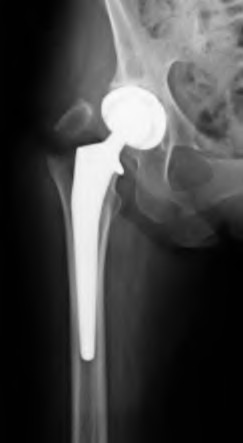

A 75-year-old female sustains a fall 5 years after a cementless THA. Radiographs show a periprosthetic femur fracture occurring around the stem tip. Intraoperative assessment reveals the stem remains firmly fixed in the metaphysis, and the proximal bone stock is adequate. According to the Vancouver classification, what is the fracture type and the standard recommended treatment?

Explanation